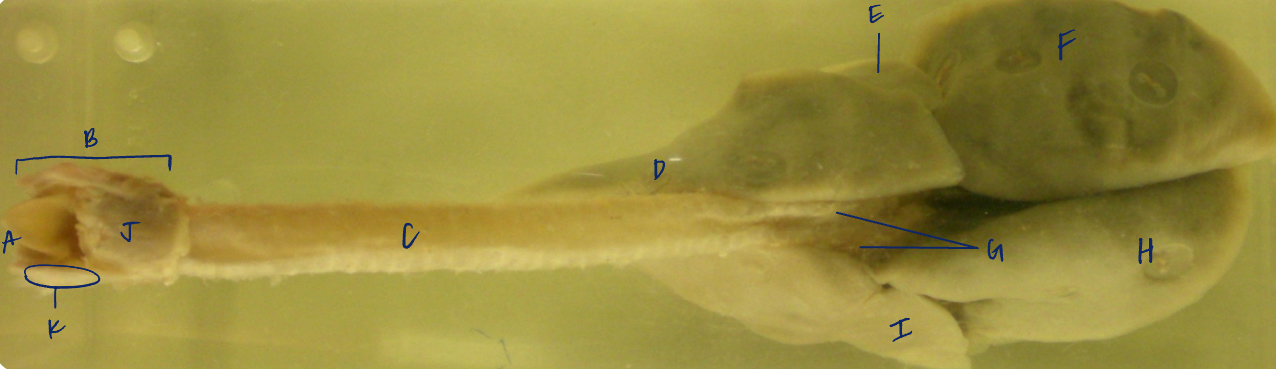

A

(dog lungs, dorsal)

L cranial lobe

B

(dog lungs, dorsal)

cranial segment, L cranial lobe

C

(dog lungs, dorsal)

caudal segment, L cranial lobe

D

(dog lungs, dorsal)

apex

E

(dog lungs, dorsal)

trachea

F

(dog lungs, dorsal)

R cranial lobe

G

(dog lungs, dorsal)

middle lobe

H

(dog lungs, dorsal)

R caudal lobe

I

(dog lungs, dorsal)

accessory lobe

J

(dog lungs, dorsal)

L caudal lobe